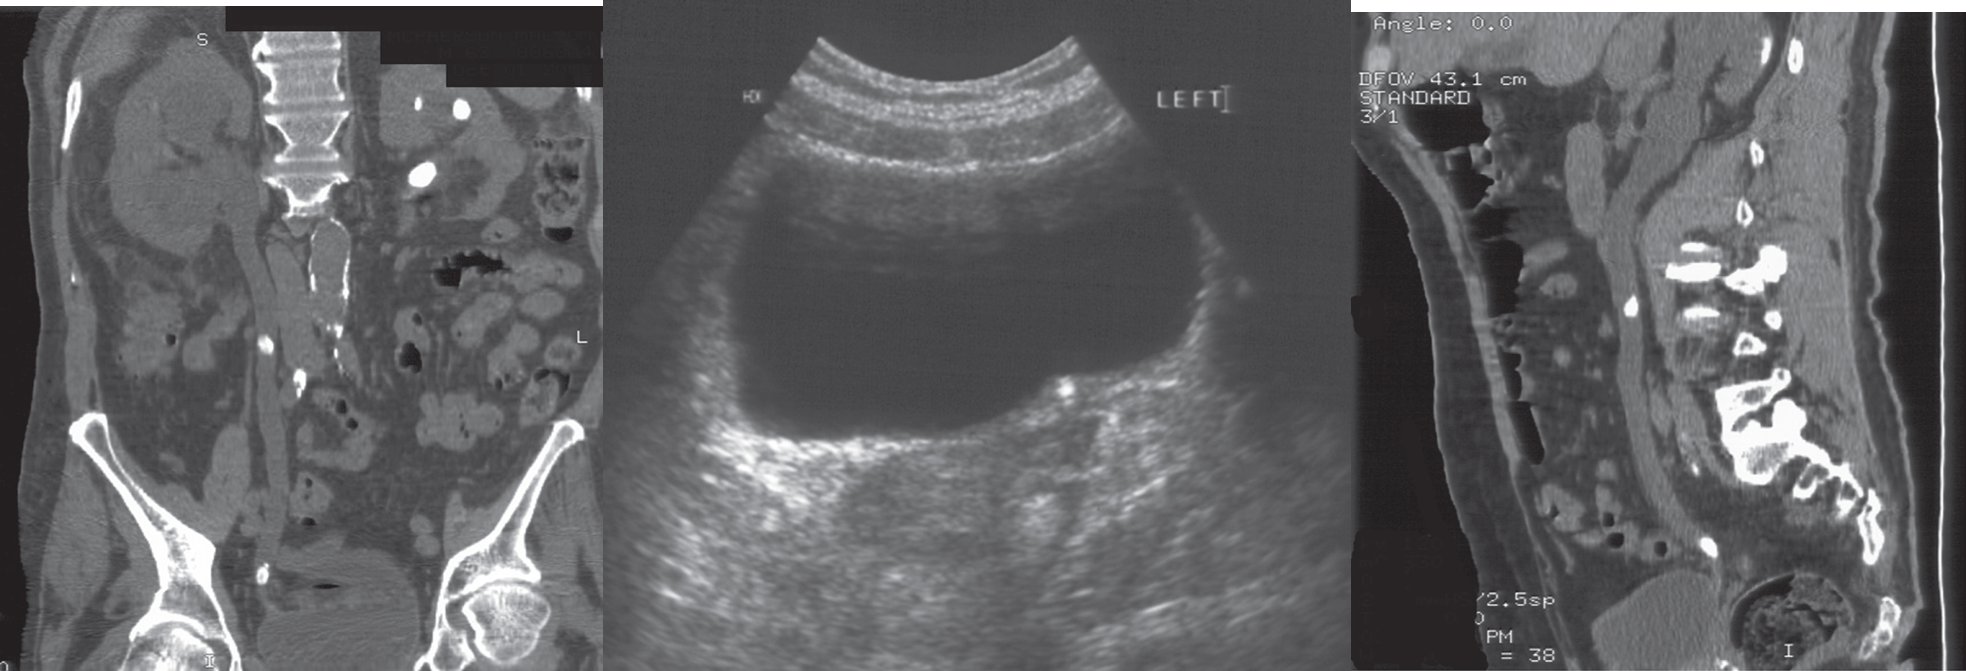

Middle age male patient presents with painless hematuria and weight loss.

- CT and ultrasound show mass lesion in left kidney

- Diagnosis: renal cell carcinoma